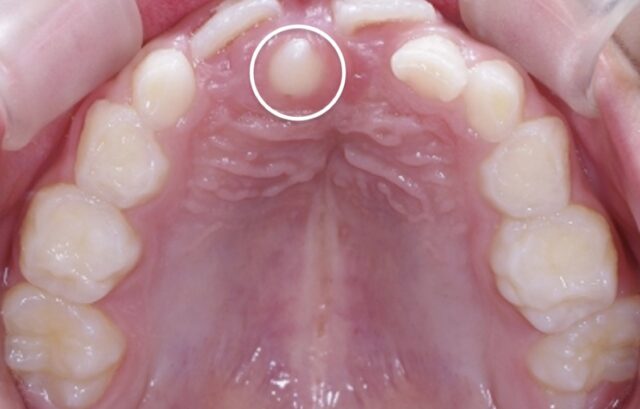

④過剰歯

過剰歯とは、正常な歯の数より多く存在する歯のことです。

上の前歯にもっともよく見られます。

乳歯の時期に発見される事が多く、その後の永久歯列に大きな影響を及ぼします。

永久歯が生えるべき場所に過剰歯が生えて来るため、スペースがなくなり歯並びや噛み合わせ、前歯が離れるなど永久歯に影響がでることがあります。

乳歯列期に過剰歯を発見してもすぐに抜歯できるとは限りませんが、早期発見が大切です。